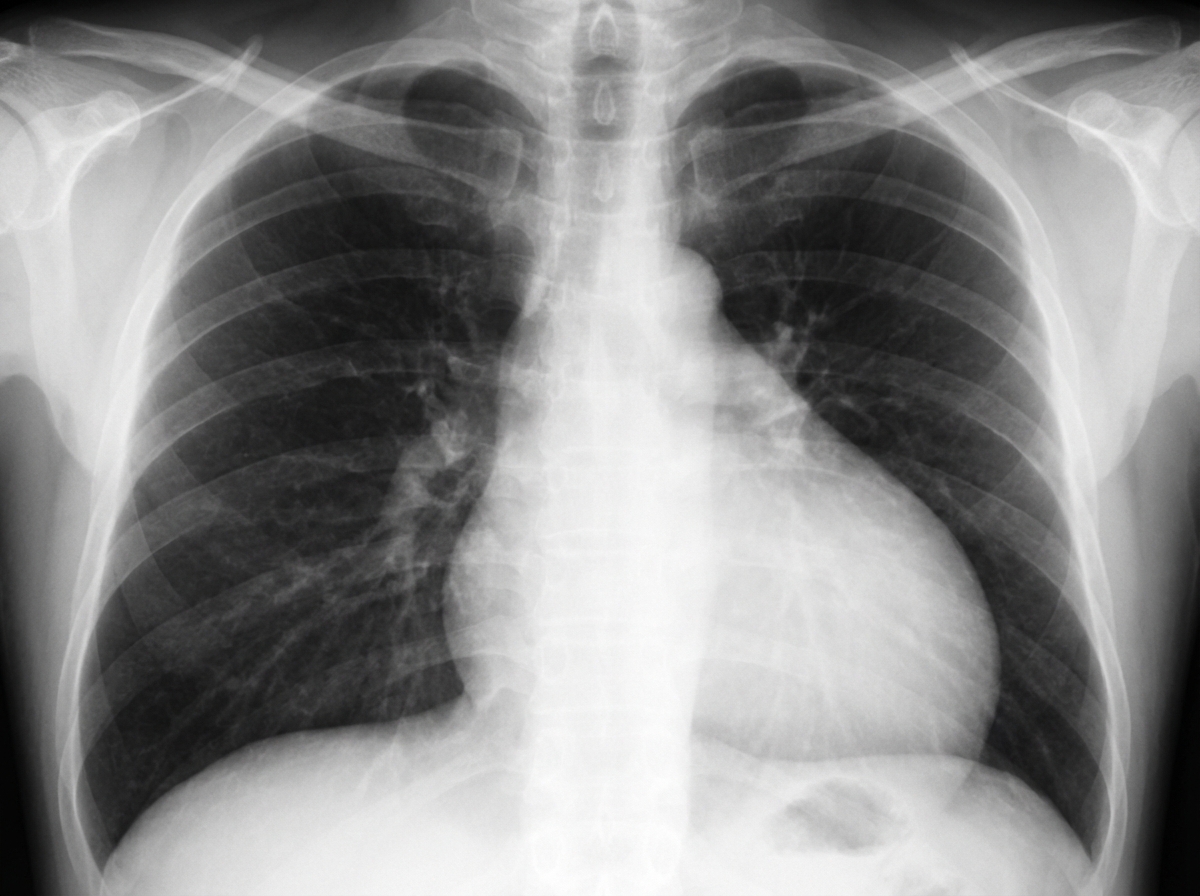

What is the most likely diagnosis based on the provided chest X-ray findings?

Explanation: ***Pericardial effusion*** - Classic **"water-bottle" or flask-shaped cardiac silhouette** on chest X-ray due to fluid accumulation in the pericardial space. - The heart appears **enlarged and globular** with loss of normal cardiac contours and waist. *Patent Ductus Arteriosus (PDA)* - Shows **increased pulmonary vascularity** with prominent pulmonary arteries and left heart enlargement. - **Left atrial and ventricular enlargement** may be present, but not the characteristic globular heart shape. *Constrictive pericarditis* - Often shows **pericardial calcification** on chest X-ray, particularly visible on lateral views. - Heart size is typically **normal or small**, not enlarged like in pericardial effusion. *Emphysema* - Characterized by **hyperinflation** with increased lung volumes and **flattened diaphragms**. - Shows **increased retrosternal airspace** and vertically oriented heart, not an enlarged cardiac silhouette.